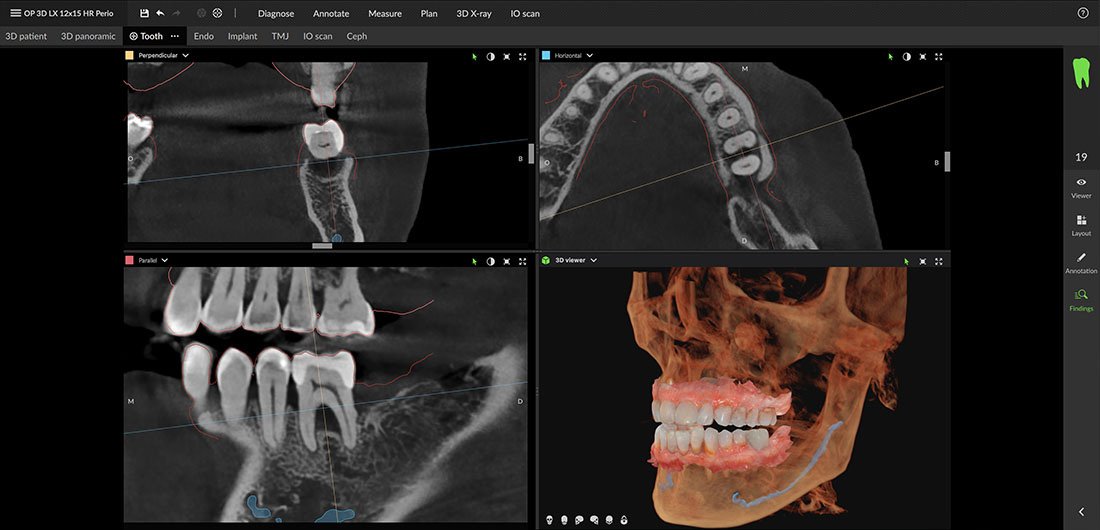

Periodontology

The OP 3D LX allows for a comprehensive examination of the bone structure, as well as the positioning of the sinus and nerves, ensuring accurate determination of treatment options for bone loss.

With its dedicated endodontic segmentation and precise scanning positioning, the DEXIS OP 3D LX is optimized to display even the smallest details, which can be crucial for endodontic diagnosis and treatment.

The evaluation of orthodontic treatments is clearer with high-resolution CBCT imaging. The DEXIS OP 3D LX aids in diagnosing complex cases by providing the most accurate positioning of unerupted or impacted teeth.